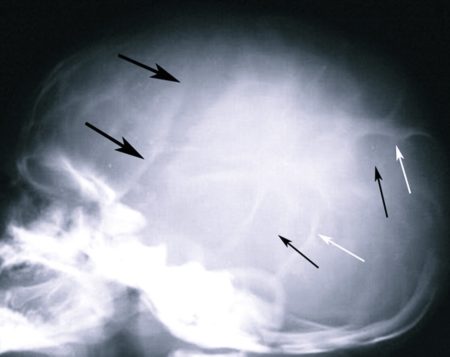

При длительном проявлении симптомов ВЧГ отек начинает распирать мозговые структуры изнутри, что в ряде случаев приводит к костным изменениям: происходит истончение пластинок черепной кости, разрушение спинки турецкого седла. Подобные особенности могут быть обнаружены во время рентгенографии.

Осмотр у врача-невролога зачастую не дает каких-либо результатов, если внутричерепная гипертензия находится на первых стадиях развития. Иногда, когда синдром ВЧГ существует у человека уже достаточно давно, неврологи могут констатировать наличие изменений рефлексов, различные расстройства когнитивных функций, симптоматику Бабинского. Но подобные проявления специфичными для ВЧГ не являются, поэтому с их помощью, без проведения рентгеноскопии и других обследований, диагностировать именно внутричерепную гипертензию будет невозможно.

- Затем больному необходимо пройти рентгенографию и получить снимок черепа. Более предпочтительным решением в этом случае является проведение КТ или МРТ, потому что с помощью этих исследований можно будет получить данные не только о костных мозговых структурах, но и о мозговой ткани, сосудах. Эти процедуры необходимы для определения первопричины повышения давления внутри черепа.